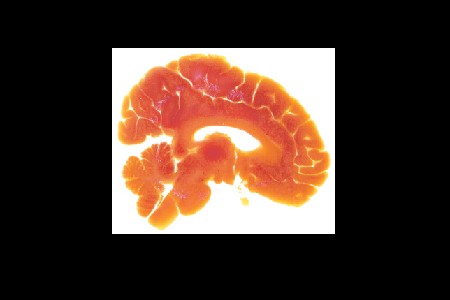

描述:正中矢狀切片